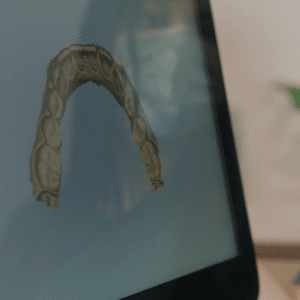

Eine Zahnaufhellung beim Zahnarzt kann auch bei Verfärbungen, wie sie auf dem Beispielfoto zu sehen sind, zu einer deutlichen Aufhellung der Zähne führen.

Bevor die eigentliche Aufhellung startet, untersuchen wir Ihre Zähne gründlich auf Karies, undichte Füllungen oder andere Zahnprobleme. Eine professionelle Zahnreinigung ist dabei fast immer die Grundlage für ein optimales Ergebnis, da sie Beläge entfernt und die Wirkstoffe besser an den Zahn gelangen lässt.

Die Zahnaufhellung selbst ist ein lichtaktiviertes Verfahren, das direkt am Behandlungsstuhl stattfindet. Dabei tragen wir ein spezielles Aufhellungsgel auf Ihre Zähne auf, welches in der Regel in drei Durchgängen mit einer Whitening-Lampe aktiviert wird. Der Vorteil: Sie sehen sofort sichtbare Ergebnisse – und das in nur etwa einer Stunde Behandlungszeit.